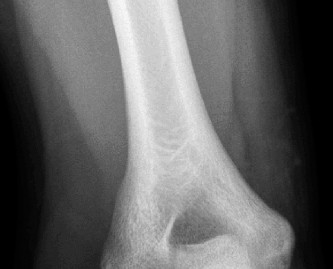

The stabilization procedure for anterior dislocations could involve: capsulolabral repair, disimpaction of the humeral head and bone grafting, size-matched allograft replacement when the remaining cartilage is healthy, or infraspinatus transfer with or without the greater tuberosity (to fill the humeral head defect) using a dual anterior and posterior approach. Similar options exist for posterior dislocations although the transfer would involve a subscapularis/lesser tuberosity transfer, which can be done entirely from an anterior approach. Additional Questions A 27-year-old banker with a seizure disorder presents to your clinic with shoulder pain and stiffness for 1.5 months since his last seizure. His X-ray is shown below (Fig. 2–46).

Figure 2–46

Which of the following is not an appropriate treatment option for this patient?

Discussion

The correct answer is (C). The image demonstrates a chronically dislocated posterior glenohumeral dislocation. At 1.5 months, a dislocation closed reduction is unlikely to be successful. Each of the answer choices shows an acceptable treatment option depending on the stability of the reduction and the size of the humeral head impaction fracture except for Answer C, open reduction and greater tuberosity transfer. This would be used for posterior defects that would be seen with anterior dislocations.